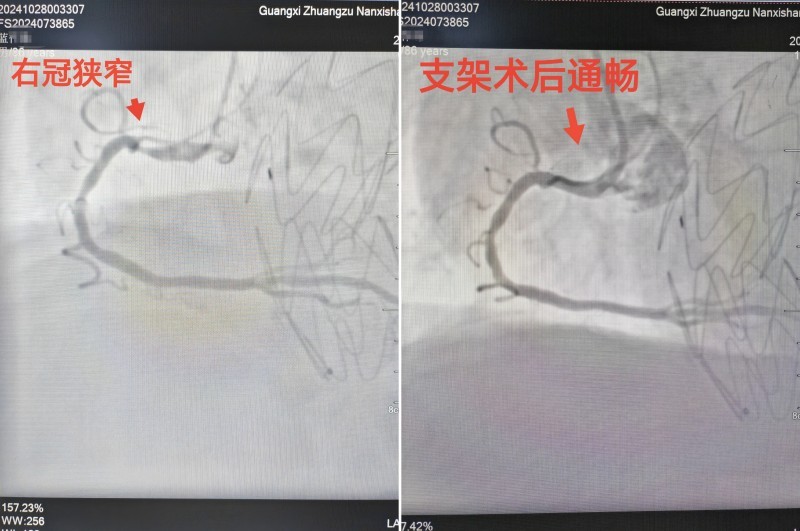

鉴于患者高龄、血管条件差且伴有阵发性胸痛症状,医生们在鉴别诊断时除了考虑胸主动脉瘤外,还高度怀疑合并冠心病可能。心电图检查也确实提示有心律失常(阵发性房颤)以及心肌缺血表现(ST段轻度抬高)。因此,需要进一步行冠脉造影以明确冠心病情况,并考虑必要时进行冠脉支架介入治疗。

随后,在心血管内科屈妍副主任医师的会诊协助下,医生们进一步为患者进行了冠脉造影检查,发现冠脉三支病变,其中右冠开口处重度狭窄。于是同期植入了一枚冠脉支架,成功疏通了冠脉血管,“通路”畅通无阻。

图片6:冠脉支架前后